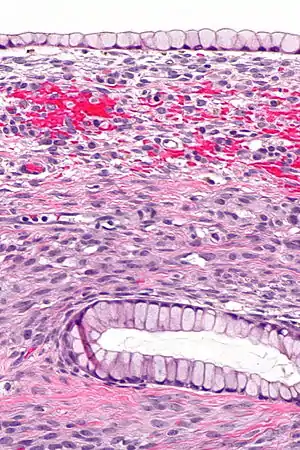

| Micrograph showing a mucinous cystadenoma of the ovary. H&E stain. | |

Mucinous cystadenoma is a benign cystic tumor lined by a mucinous epithelium.